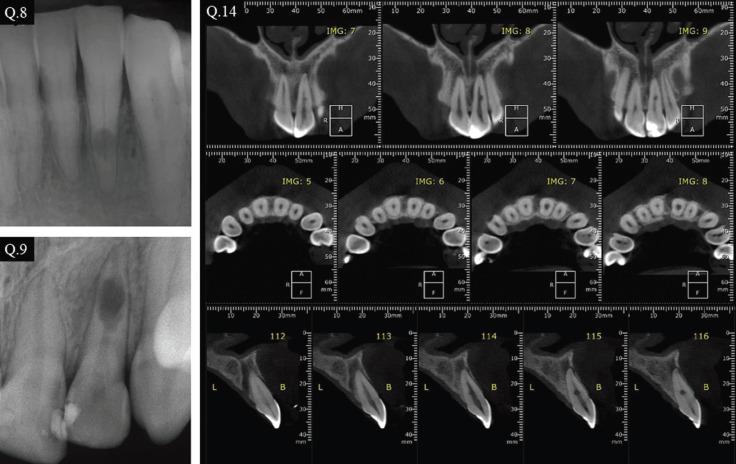

This study assesses and compares the knowledge level of endodontists (ENDs) and general dental practitioners (GPs) from Brazil and United States of America (USA) in the diagnosis and treatment of internal and external inflammatory root resorptions through periapical radiographic (PA) and cone beam computed tomography (CBCT) examinations.

A cross-sectional online questionnaire-based survey was presented to the volunteers containing questions regarding personal and professional profile, as well as three clinical cases of internal and external inflammatory root resorption. A series of multiple-choice questions about the diagnosis and treatment options were surveyed. The data collected was analysed by the Chi-square test with Yates correction with a significance level of 5 %.

本研究评估并比较了巴西和美国的牙髓病医生(ENDs)与普通牙科医生(GPs)通过根尖片(PA)和锥形束计算机断层扫描(CBCT)检查诊断和治疗内、外炎性牙根吸收的知识水平。

向志愿者发放了一份基于在线问卷的横断面调查,问卷包含有关个人和专业背景的问题,以及三个内、外炎性牙根吸收的临床病例。调查了一系列关于诊断和治疗选择的多项选择题。收集的数据采用经Yates校正的卡方检验进行分析,显著性水平为5%。